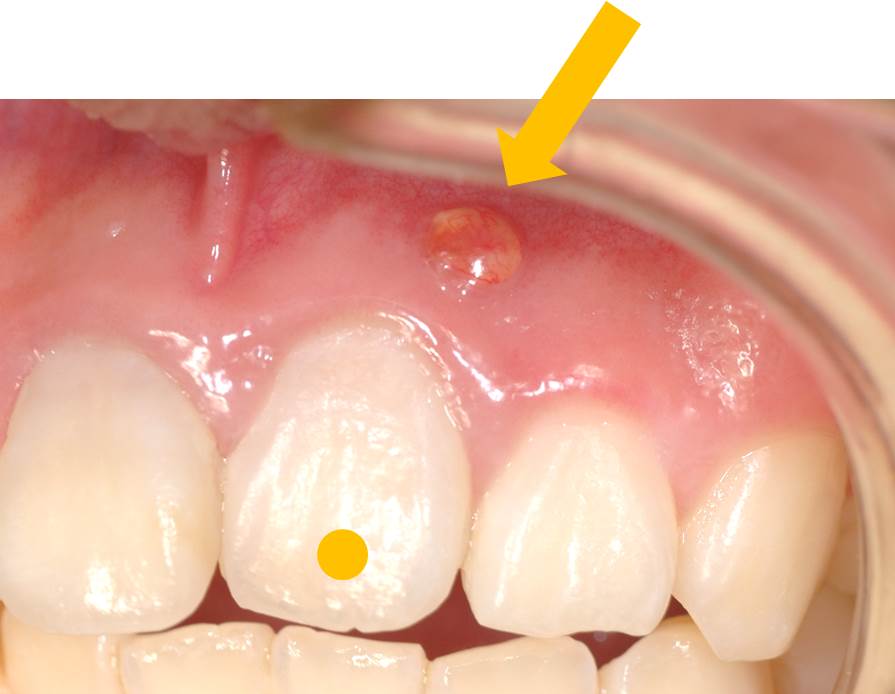

写真の矢印の部分を見ていただくと、歯茎から膿が出てきています。

次の2つのことが考えられます。①歯周病(歯周炎) ②根尖病巣(虫歯が原因で神経を取った歯)のどちらかの疾患が予想されます。今回はどちらでしょうか?

ですから、今回のケースでは、①歯茎からの膿、②歯周ポケットがない、③神経(血管も)を取った歯であるため、歯周病ではなく「根尖病巣」といって歯の中で増えた細菌が原因ということが分ります。